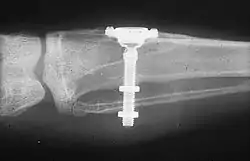

In the 1950s research was being conducted at Cambridge University in England on blood flow in living organisms. These workers devised a method of constructing a chamber of titanium which was then embedded into the soft tissue of the ears of rabbits. In 1952 the Swedish orthopaedic surgeon, Per-Ingvar Brånemark, was interested in studying bone healing and regeneration. During his research time at Lund University he adopted the Cambridge designed "rabbit ear chamber" for use in the rabbit femur. Following the study, he attempted to retrieve these expensive chambers from the rabbits and found that he was unable to remove them. Brånemark observed that bone had grown into such close proximity with the titanium that it effectively adhered to the metal. Brånemark carried out further studies into this phenomenon, using both animal and human subjects, which all confirmed this unique property of titanium. Leonard Linkow, in the 1950s, was one of the first to insert titanium and other metal implants into the bones of the jaw. Artificial teeth were then attached to these pieces of metal.[13] In 1965 Brånemark placed his first titanium dental implant into a human volunteer. He began working in the mouth as it was more accessible for continued observations and there was a high rate of missing teeth in the general population offered more subjects for widespread study. He termed the clinically observed adherence of bone with titanium as "osseointegration".[14]: 626 Since then implants have evolved into three basic types:

- Root form implants; the most common type of implant indicated for all uses. Within the root form type of implant, there are roughly 18 variants, all made of titanium but with different shapes and surface textures. There is limited evidence showing that implants with relatively smooth surfaces are less prone to peri-implantitis than implants with rougher surfaces and no evidence showing that any particular type of dental implant has superior long-term success.[15]